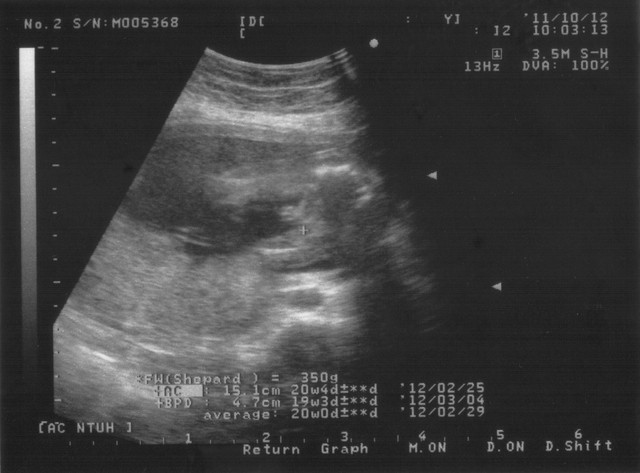

寶寶己經長大很多了

一張超音波照己經無法容下

這次拍了四張超音波照

體重:190g

FL大腿骨的長度:2.3CM

AC腹圍的長度:12.2CM

BPD頭骨橫徑:3.5 CM

以上一切正常

我20w的產檢其實也己經做好了

己經確定是男生了